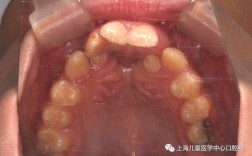

正畸治疗是唇腭裂序列治疗的基础,贯穿患者生长发育的不同阶段,需根据年龄、畸形程度及颌骨发育情况制定个性化方案,乳牙期(3-6岁)的治疗以预防为主,主要针对上颌骨发育不足导致的反颌,通过活动矫治器或扩弓器扩大狭窄的上颌牙弓,纠正前牙反,避免反颌限制上颌骨发育,同时纠正下颌前伸习惯,为后续颌骨发育创造空间,此阶段治疗周期较短,通常6-12个月,可显著降低替牙期严重错的发生率,替牙期(7-12岁)是颌骨发育的关键期,患者常出现牙弓不对称、牙列间隙不足、牙槽突裂等问题,治疗重点包括:通过固定矫治器排齐牙列、纠正中线偏斜,为牙槽突植骨术做准备(植骨通常在9-12岁进行,需确保植骨区域牙根发育完成);利用生长潜力,通过前方牵引装置促进上颌骨向前发育,改善上颌后缩畸形,对于合并下颌偏斜的患者,可配合功能性矫治器(如FRⅢ矫治器)调整下颌位置,建立协调的颌骨关系,恒牙早期(12-18岁)颌骨发育接近成熟,此时需进行全面的正畸治疗,通过固定矫治器精细调整牙列,解决牙列拥挤、扭转、深覆等问题,为正颌手术创造理想的咬合条件(即“去代偿治疗”,将移动至异常位置的牙齿调整至正常颌骨关系中的位置),成人期(18岁后)颌骨已停止发育,若存在严重颌骨畸形,需在正颌手术后进行术后正畸,稳定手术效果,确保咬合关系的长期稳定,不同年龄阶段的治疗目标和方法可总结如下: